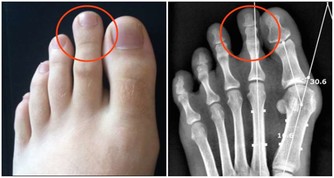

當頸椎曲度病態變直或扭曲,椎體間隙受擠壓而變小,椎間盤受擠壓而膨出,椎體骨質增生,

會刺激神經,誘發眩暈、頭痛、手臂麻木,甚至截癱。